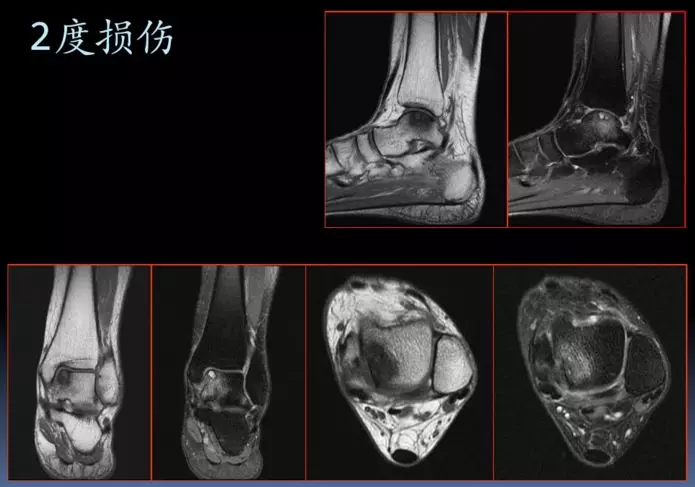

踝关节外侧韧带急性损伤的mri表现

图片尺寸1080x810